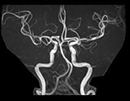

脳動脈瘤、脳腫瘍、脳梗塞などの診断に役立ちます。

造影剤を使用せず脳の血管の状態を見ることができ ます。

この検査の所要時間は40分程度です。